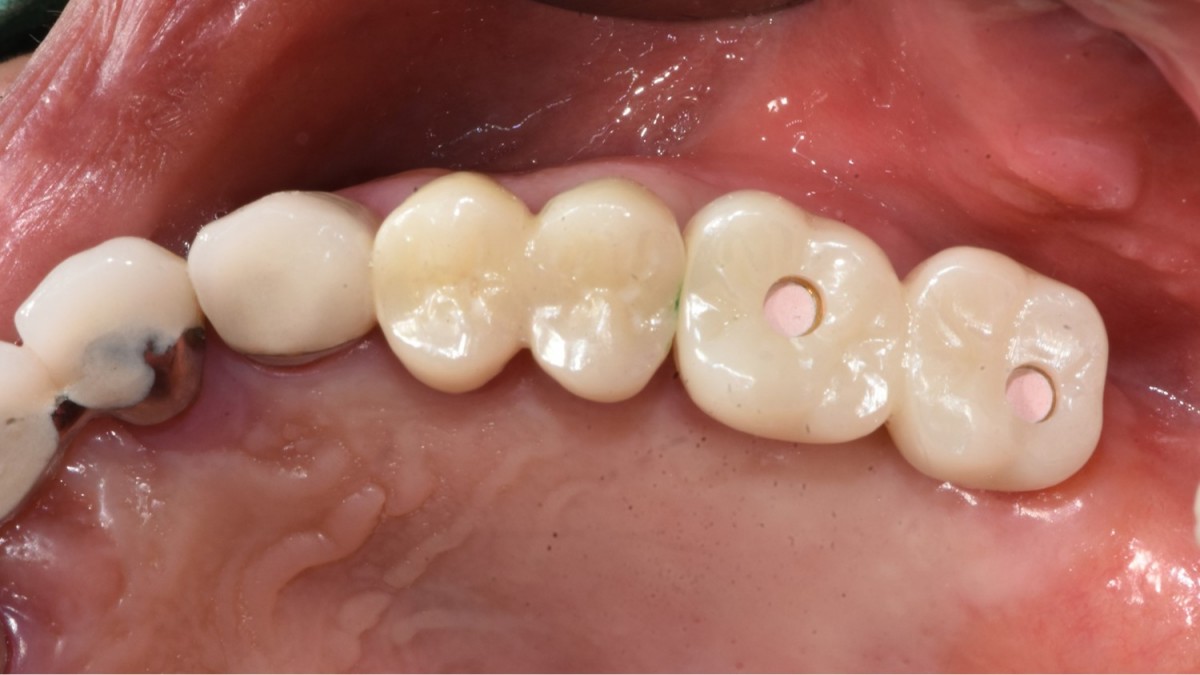

▲2 implants were placed. ArumDentistry NB1 5*10 (30Ncm) in the 1st molar and 5*10 (10Ncm) in the 2nd molar.